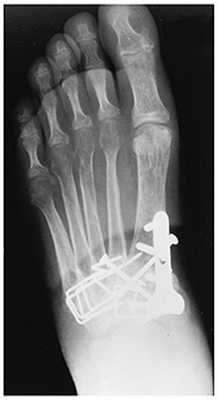

При смещении более 2 мм, нестабильности при функциональных тестах – рекомендовано открытое устранение вывиха с жёсткой фиксацией винтами или пластинами. Используются один или два продольных доступа в 1 и 2 межплюсневых промежутках. После обнажения первого предплюсне-плюсневого сустава первым этапом устраняется межклиновидная нестабильность, вторым этапом устраняется предплюсне-плюсневая нестабильность. В послеоперационном периоде сразу начинается разработка активного объёма движений. Нагрузку на стопу начинают постепенно, с тем чтобы полностью её восстановить к 6-8 неделе. Удаление спиц Киршнера производится через 6-8 недель, компрессирующих винтов через 3-6 месяцев. Возвращение к полной физической активности не ранее 9-12 месяцев после операции.

Открытое вправление вывиха, трансартикулярная фиксация 1-2-3 предплюсне-плюсневых суставов винтами.

После восстановления 2 луча выполняем артродез межклиновидного сустава и 1 плюсне-клиновидного сустава. Учитывая что основная нагрузка ложится на 1 луч, дополнительно стабилизируем его при помощи пластины.

![артродез сустава лисфранка]()